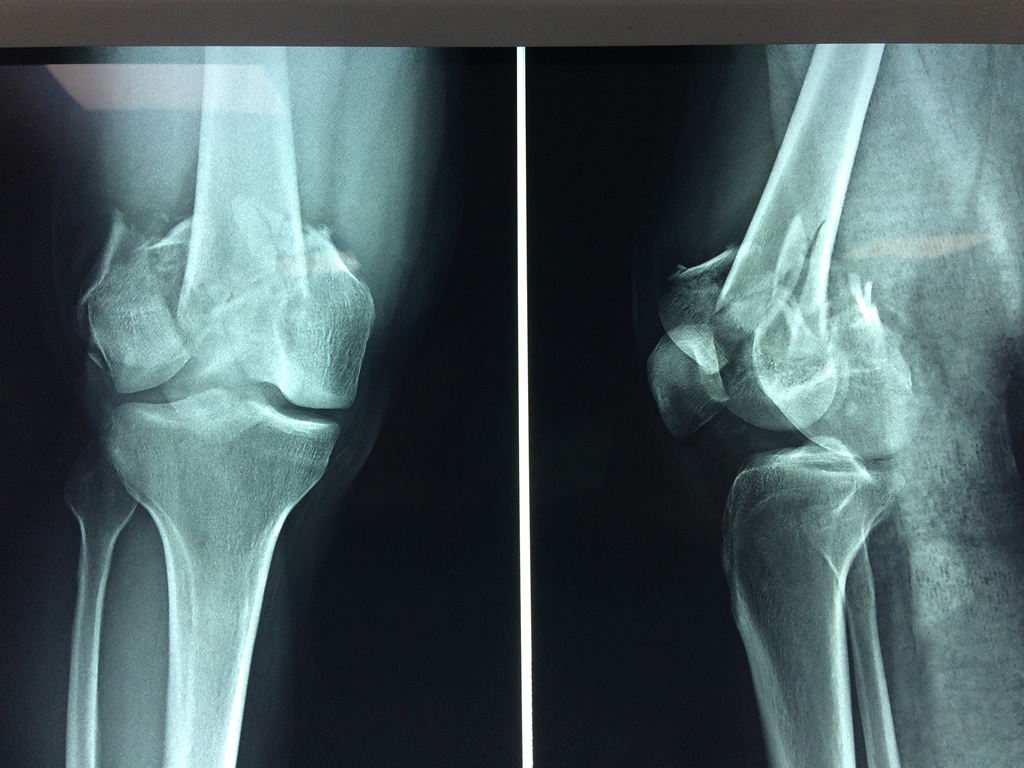

Cirugías de Codos - Fémur

El fémur es el hueso del muslo, el segundo segmento del miembro inferior. Es el hueso más largo, fuerte y voluminoso del cuerpo humano.